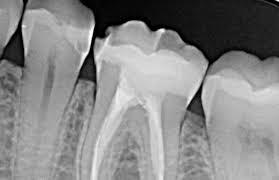

Dr.C.Edmund Kells-Fue el primero en realizar una radiografía intraoral y verificar si un conducto radicular había sido obturado.